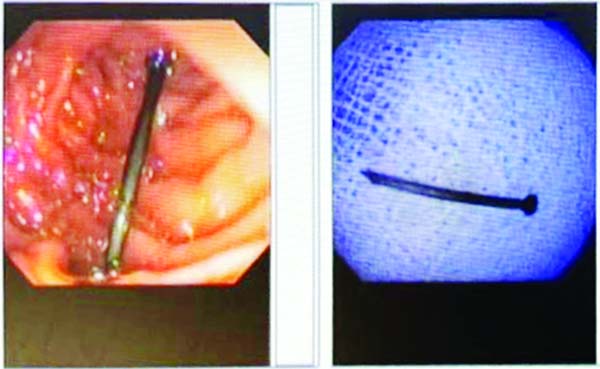

JAMMU, Jan 11: Renowned Gastroenterologist Dr Shoket Chowdhary today removed nail swallowed by a teenager from his abdomen without surgery using Endoscope.

The procedure was performed by Dr Chowdhary over a 14-year-old boy who swallowed the nail accidentally using Endoscopic procedure at ARV Multispecialty Hospital Sidhra,